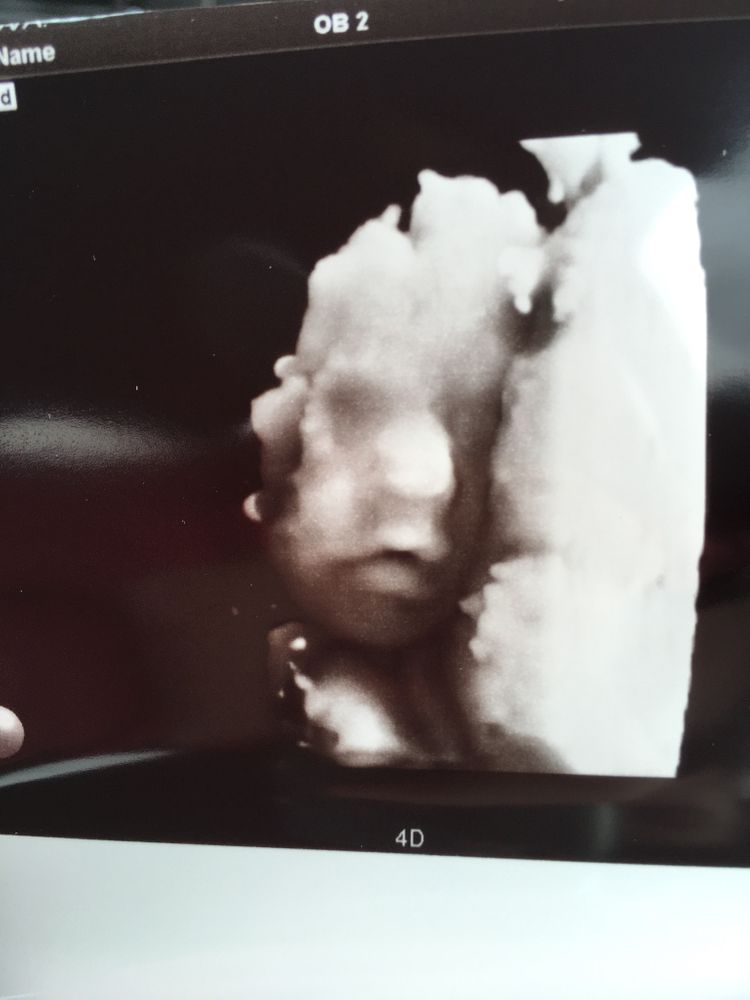

Мать добриков, ну 3д можно и на первом скрининге сделать, но там скорее пришелец, чем человек 😁я то хочу красивое фото- приближённее к тому, как будет выглядеть малыш после рождения. Вот в 26 недель младший